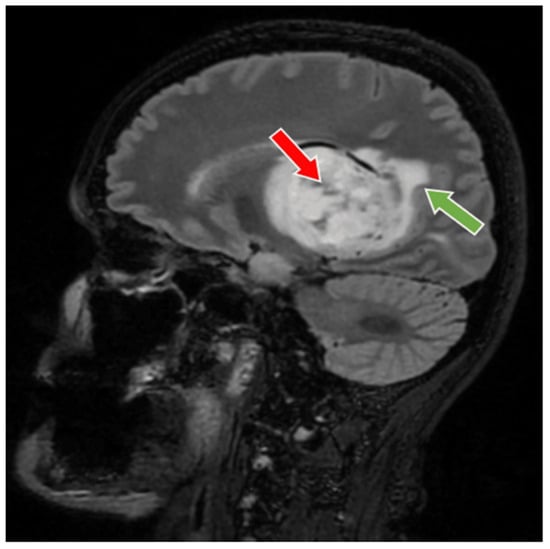

2. Case Presentation